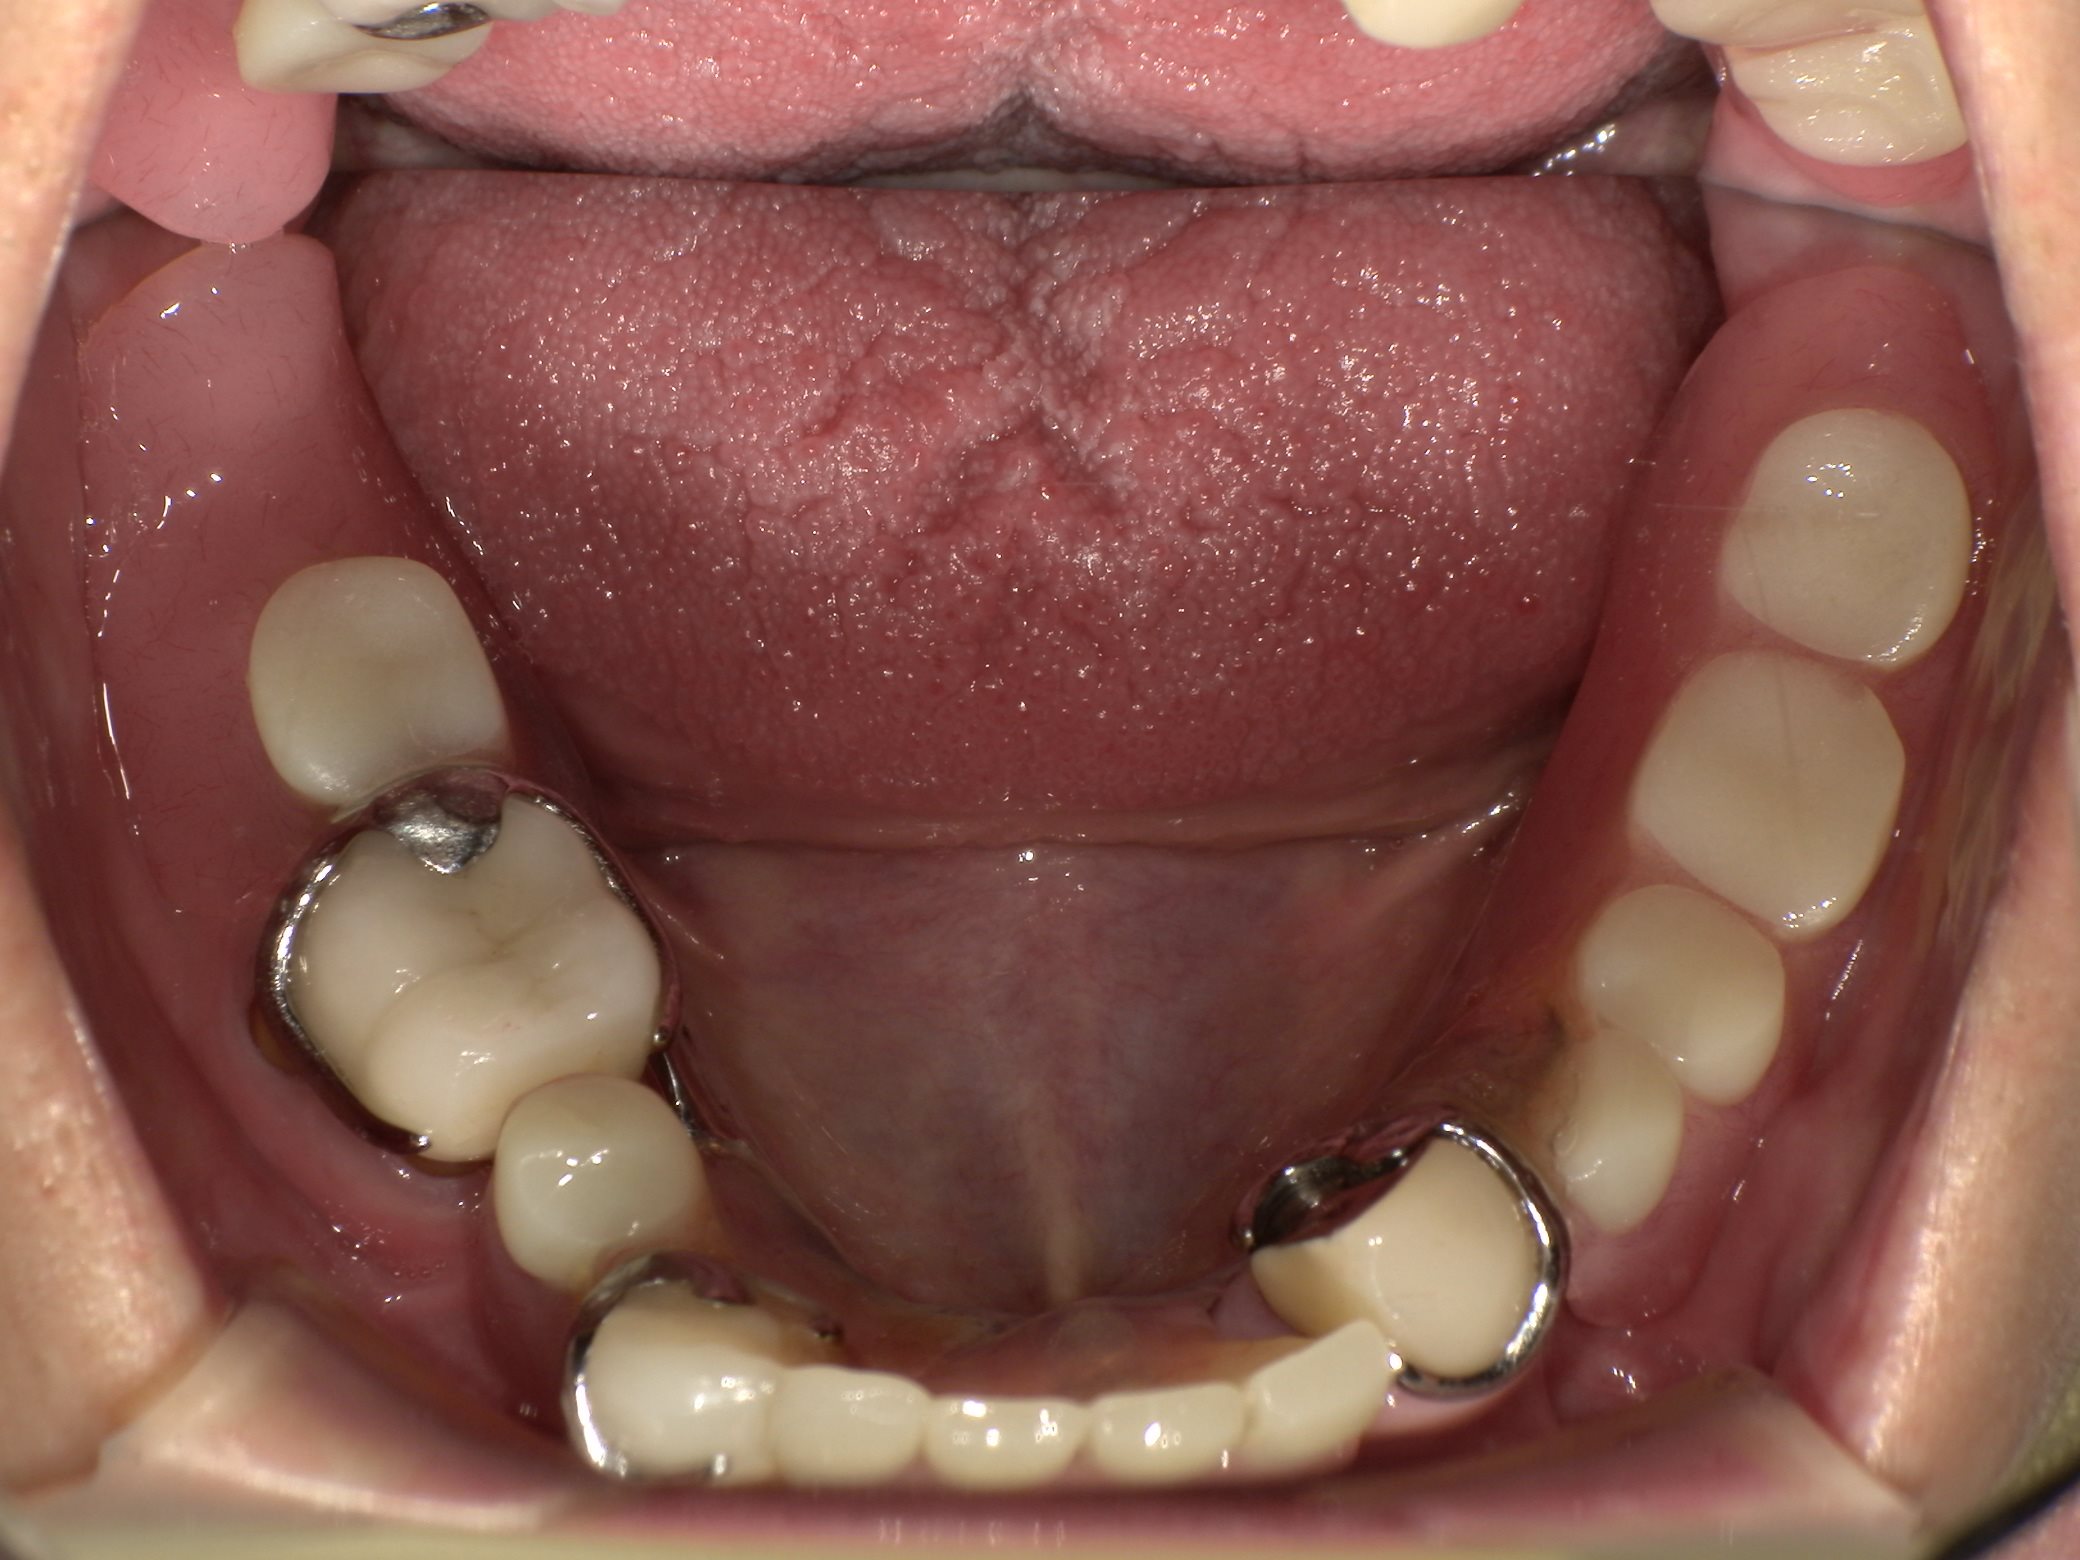

治療前の口腔内写真です。

下の歯は2本のみ残存しており、その部分に入れ歯をかけている状態でした。

正面から口元を見ると、歯にかけている入れ歯の金具があるのが分かります。